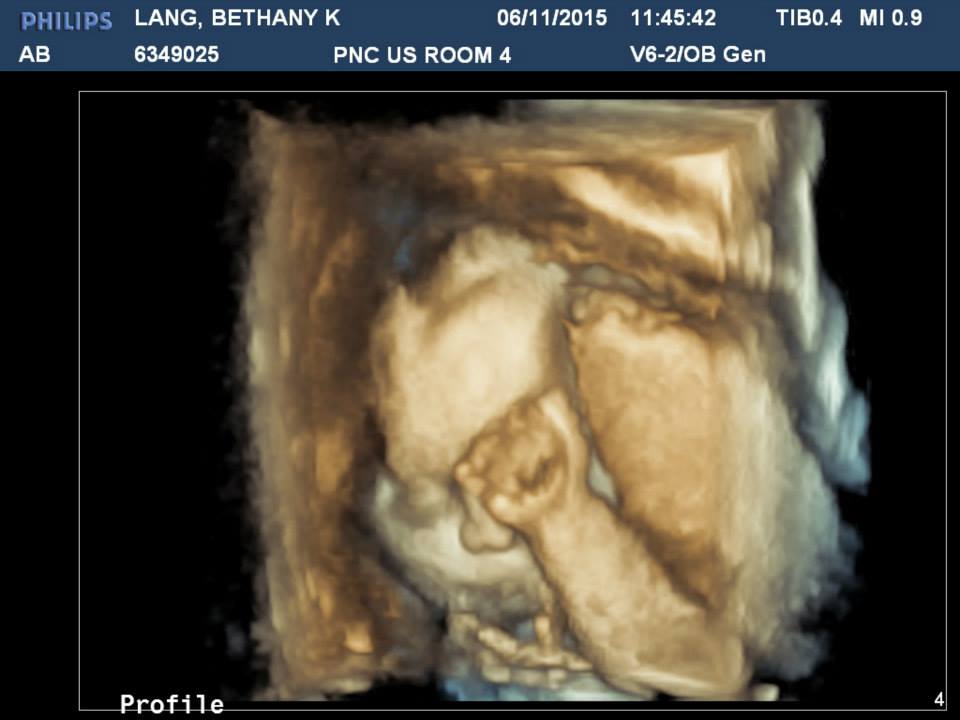

Well I had my ultrasound. She's in the 82 percentile and they measured her about a week ahead but nothing too significant. They're keeping my due date. But I got to see her again and they did a bunch of 3D images which was fun, she just wouldn't move her hand. They also said she has a ton of hair already. That was neat to see.